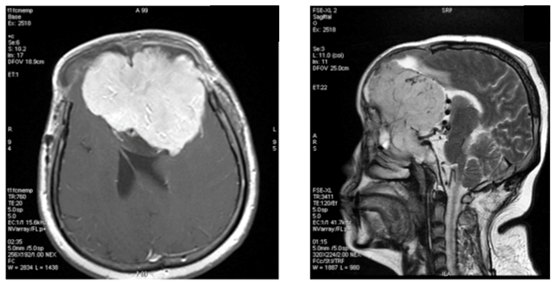

In our study showed that tumor volume as suggested by Hale et al. as the strongest predictor of atypical meningioma, didn’t always correlate with meningioma grade. In our samples there were 6 (37.5%) meningioma WHO grade I with tumor volume more than 50 cm3, with the biggest volume 252.4cm3 (Figure 1) and 1(33%) of atypical meningioma (WHO grade II) with tumor size 28.5 cm3. Hale also suggested that peritumoral edema as predictor of higher grade meningioma. In our study we found 1 case of anaplastic meningioma (WHO grade III) with mild edema and conversely, 44% of meningioma WHO grade I with severe edema (Figure 2). In that study also found that tumor along the falx and convexity were more often atypical than in skull base or posterior fossa. In this study, samples of meningioma WHO grade I mostly (37.5%) located in convexity, 25% in falx and in atypical meningioma WHO grade II turned out 67% located in skull base (Figure 3). That study also found that tumor necrosis was associated with an increased risk for atypical meningioma. In this study, we found 67% of atypical meningioma WHO grade II without tumor necrosis and 44% of typical meningioma WHO grade I with tumor necrosis (Figure 4). 1 case of anaplastic meningioma (WHO grade III) in our study had large tumor volume (>50 cm3), located in convexity and with tumor necrosis although there was one predictor that didn’t suit which in this case had mild peritumoral edema (Figure 5).

Figure 5 Male, 21 y.o, tumor vol 190.2 cm3 with mild peritumoral edema, located at left frontoparietal convexity, tumor necrosis (+), turned out to be meningioma anaplastic type, WHO grade III.